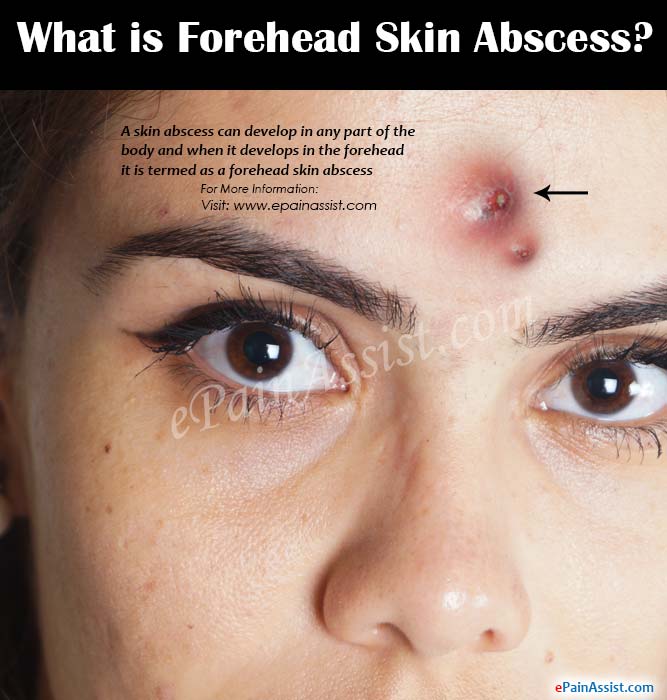

What is Forehead Skin Abscess|Causes|Symptoms|Treatment|Prevention